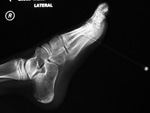

| Nail in foot |

| Young man wearing sandals stepped on a nail. The nail penetrated his plantar soft tissues but this radiograph showed it had not entered bone. From Hunter, 1994 |